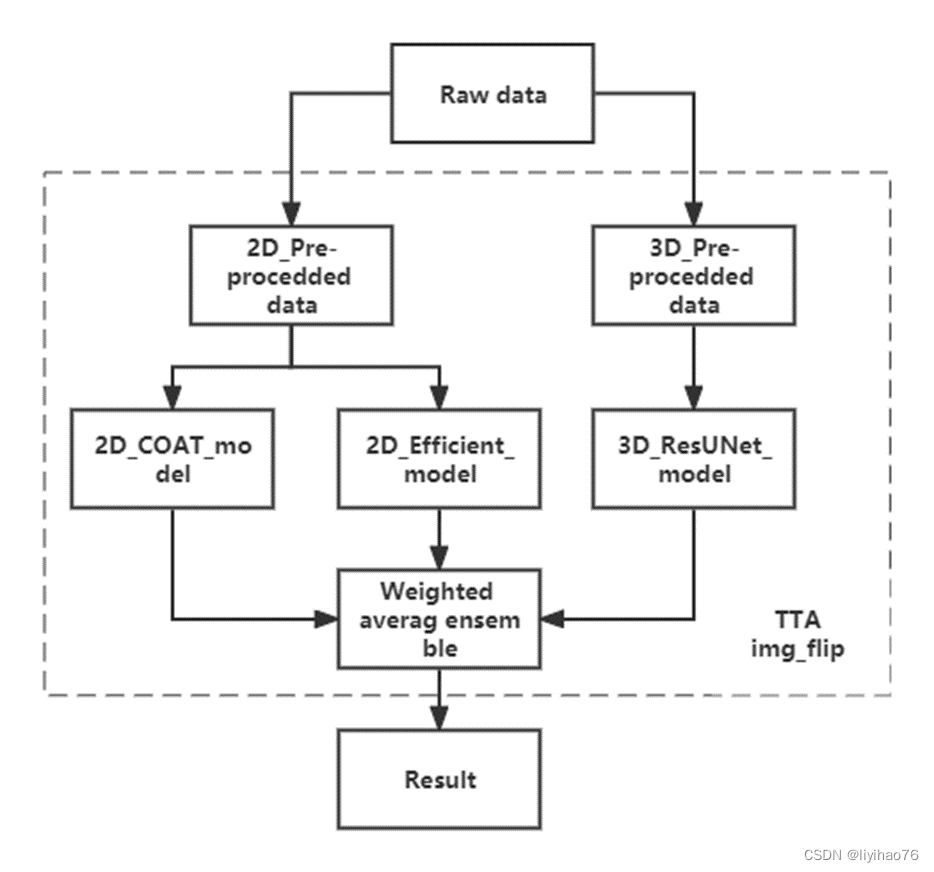

整体程序流程如图所示:

总体方案可以分为两部分,即2D模型部分和3D模型部分。

2D部分首先对原始数据进行2D数据预处理,将原始3D图像正则化为16进制深度的2D图像,经过图像裁剪和CLAHE增强后送入2D模型。 二维模型有两类,分别是COAT_Unet模型和efficientb6_unet模型。

在3D部分,首先对原始数据进行16进制数据正则化、图片裁剪和CLAHE增强处理,然后送入3D模型。 3D模型使用ResidualUNet3D。

这些模型的融合使用加权平均集成方案,我们使用 TTA(Test Time Augmentation)技术来改进我们的方案结果。